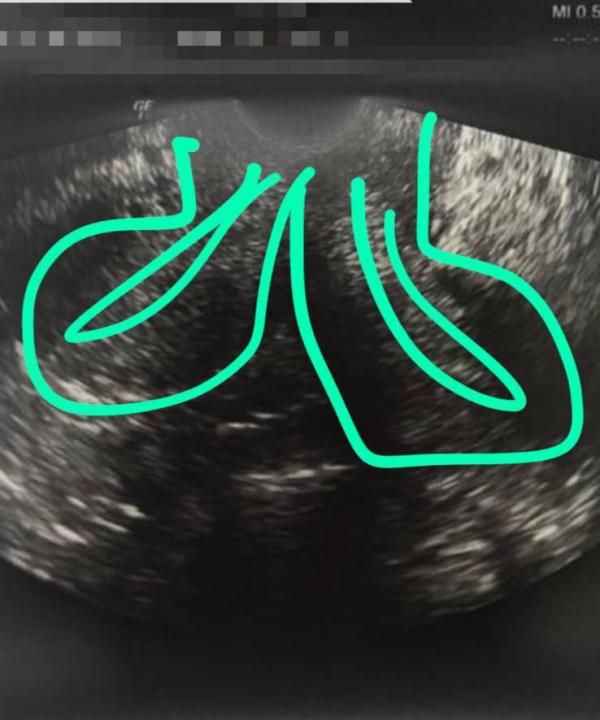

Пациентка, работает учителем в школе, ежегодно в течение 10 лет проходила проф.осмотры. Без особенностей.

Обратилась с жалобами на нарушение менструального цикла. При осмотре выявлено полное удвоение матки и шейки матки…

Женщина ведь ежегодно сдавала цитологию шейки матки. Вопрос «Из какой шейки»…? Правой или левой?🤦🏼♀️Получается, скрининг на рак брали из какой?

Я вот не понимаю, это как можно не заметить? 2 полноценные матки и...